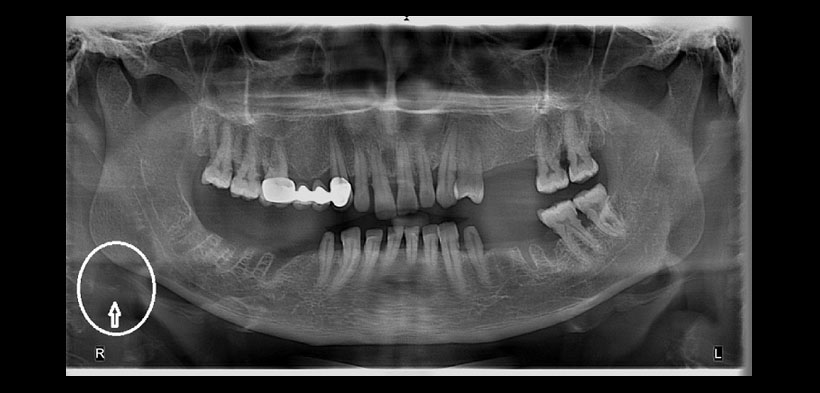

Fig. 2. Radiografía panorámica de un paciente de 56 años de edad. Se evidencia una imagen radiopaca unilateral derecha, por debajo del ángulo mandibular, compatibles con probable ateroma dentro de la arteria carótida (círculos blancos).